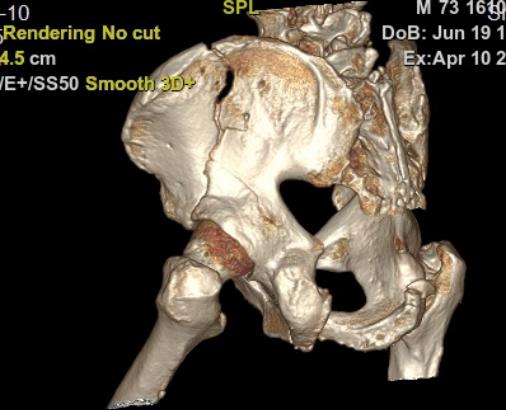

手术前,团队通过三维CT扫描获取骨盆精准影像,在电脑上规划出最佳的螺钉置入路径。骨科手术机器人接收指令后,机械臂精确定位,仅通过两个硬币大小的微创切口(约1.5厘米),在实时引导下顺利完成了髂骨螺钉及LC‑Ⅱ螺钉的置入。整个手术不到2小时,出血量仅约10毫升。